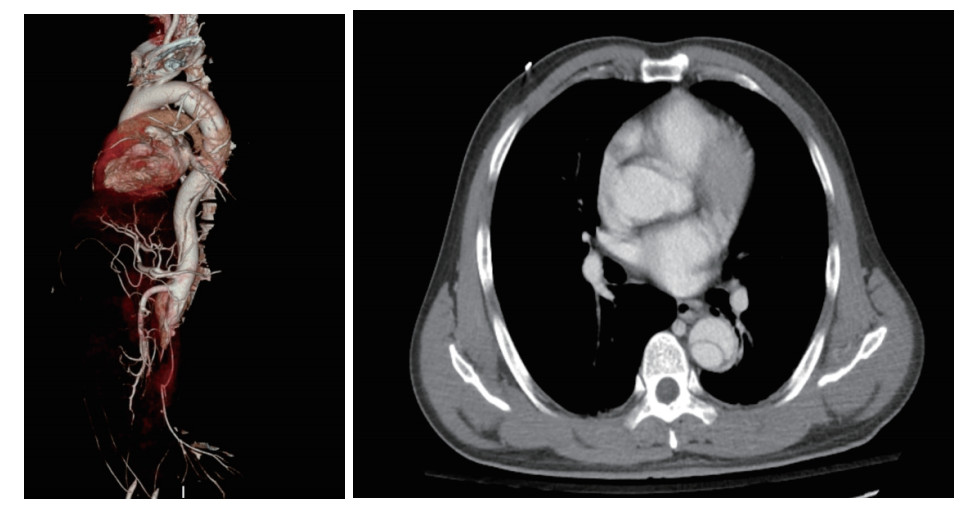

1 资料与方法患者,男,49岁,因“重物砸伤致双下肢活动障碍1 d余”于2021-11-27入本院。患者1 d余前不慎被约拳头大小的石块从约十米高坠落砸伤腰背部,当时感腰背部疼痛,约10 min后双下肢逐渐出现活动障碍,伴感觉减退及肢体麻木。送至当地医院急诊,患者入抢救室生命体征平稳,问诊既往体健,无重大手术史;根据受伤机制考虑胸腰椎损伤,完善胸腰椎CT及磁共振后未见明显异常,患者下肢活动障碍逐渐加重(肌力1级),并伴有肢端循环障碍,但未予进一步处理。患者在当地医院给予补液、止痛等对症治疗后下肢肿胀进一步加重,家属要求转入本院继续治疗。急诊查体:神志正常,急性面容,普通面罩吸氧5 L/min,氧饱和度92%~94%;心率102次/min,呼吸频率25次/min,血压190/103 mmHg(1 mmHg=0.133 kPa),心肺听诊阴性;腹软,腹部轻压痛,后背部压痛明显,双上肢肌力Ⅴ级,双下肢肌力0级,腹股沟以下感觉平面不存在,具体病理征没有出现。急诊血液检验:血常规:白细胞17.6×109 /L, 中性粒91%,血红蛋白151 g/L; 凝血功能:D二聚体 > 20 000, INR 1.16, APTT 42.6 s,TT 24.7 s;急诊生化和心肌酶谱:血钾7.47 mmol/L,肌酸激酶325 900 U/L、肌酐170.0 μmol/L、谷丙转氨酶1 560 U/L、谷草转氨酶7 240 U/L、肌钙蛋白2.26 ng/mL;血气分析: pH 7.3, BE -11.9 mmol/L,PaO2 95.9 mmHg, PaCO2 25.1 mmHg; 心电图提示:下、前侧壁ST段、T波变化,前间壁T波高耸(考虑心电图变化与患者高钾有关),入急诊后患者神志淡漠,血氧氧饱和度进行性下降,立即予气管插管呼吸机辅助通气维持呼吸。急诊行主动脉CTA诊断为胸腹主动脉夹层动脉瘤形成:Debake Ⅲ型:第一破口位于主动脉弓降部以远(图 1),腹主动脉远段、左肾动脉、肠系膜下动脉及双侧髂动脉腔内血栓考虑,右侧髂血管周围渗出,左侧肾动脉灌注欠佳。立即联系血管外科会诊,但因患者血钾极高,严重酸中毒,循环不稳定(去甲肾上腺素0.89 μg/(kg·min);建议纠正内环境,待情况允许后急诊行主动脉夹层腔内修复术,以“创伤性主动脉夹层(Debake Ⅲ型)、高钾血症、横纹肌溶解症、多脏器功能衰竭”收入急诊ICU。

| 图 1 胸主动脉+腹主动脉造影 |